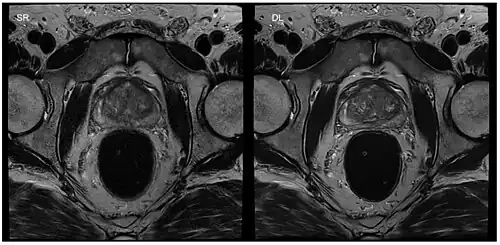

Although applications of real-time MRI cover a broad spectrum ranging from non-medical studies of turbulent flow[27] to the noninvasive monitoring of interventional (surgical) procedures, the most important application making use of the new capabilities is cardiovascular imaging.[1] Previous cardiac MR (CMR) used cine techniques to capture the periodic motion of the heart. However, this is not feasible for patients with arrhythmia, where the cardiac cycle is unpredictable.[28] With the new method it is possible to obtain movies of the beating heart in real time with up to 50 frames per second during free breathing and without the need for a synchronization to the electrocardiogram.[29] A study performed by Laubrock et al.[28] demonstrated that RT-MRI produced higher quality images with a higher SNR than cine CMR with a bSSFP sequence and radial k-space sampling. RT-MRI also removes the need for breath-holding while imaging, leading to a more comfortable experience for the patient as well.[28]